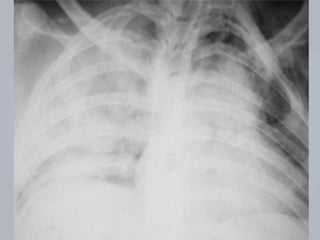

CONTUSÃO PULMONAR

 Laceração ou rompimento  mec. contusos ou

penetrantes;

 Sangue nos alvéolos e entre eles  dificuldade na

troca gasosa;

 Complicação comum e potencialmente letal;

 AVALIAÇÃO: os achados são variáveis; avalição

inicial pode não revelar dificuldade respiratória;

observar presença de retalho costal móvel.

 TRATAMENTO:

 Suporte ventilatório;

 Oximetria de pulso e capnografia;

 Reanimação volêmica  cautelosa ( edema) 

comprometimento da ventilação e a oxigenação.